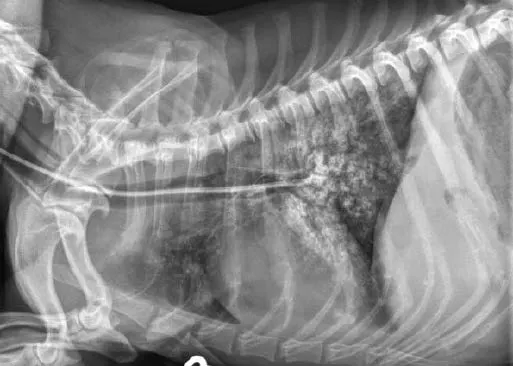

Verify tube location with survey (A) or contrast (B) radiography. Inject 2–3 mL of iohexol or other nonionic, iodinated contrast medium into the tube, followed by 3–5 mL of air or sterile saline. Note how the contrast medium highlights the esophageal folds.

Author Insight

When an NE tube is placed appropriately, its end is located at the eighth intercostal space (approximately). Even properly placed tubes can appear to be in the airways, because the esophagus overlies the trachea and bronchi on caudal cervical and thoracic radiographs.

In this dog, the proximal end of the tube is not associated with the trachea.